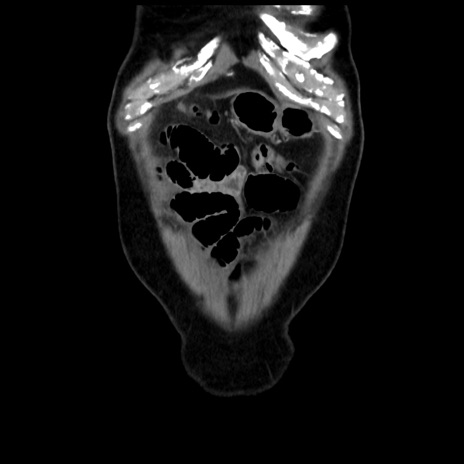

症例16(冠状断像)

【症例】 70歳代男性

【主訴】 腹痛、嘔吐

【現病歴】 約1ヶ月前より間欠的に腹痛と嘔吐あり、当院消化器内科を受診したところCTで多発する肝臓のLDAを指摘され、精査中であった。以降は消化器症状は安定していたが、2日前より嘔気と腹痛があり、同日より排便・排ガスが消失した。改善認めず、 本日、救急外来を受診した。

【既往歴】 大腸ポリープ切除後。

【身体所見】意識清明・会話良好、BT 36.3℃、BP 127/80mmHg、 P 80bpm、腹部:膨満あり、平坦・軟、上腹部正中および下腹部正中に圧痛あり、反跳痛なし、筋性防御なし。

【データ】WBC 7200、CRP 0.77